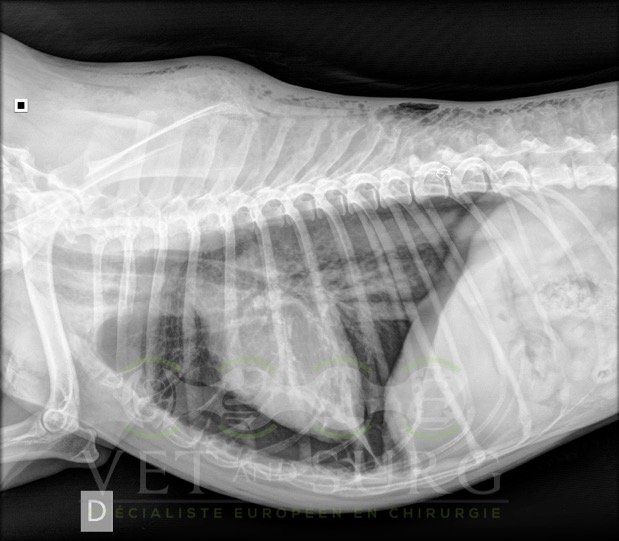

Dans la gestion des pathologies respiratoires, cardio-vasculaires, et des atteintes médiastinales et diaphragmatiques.